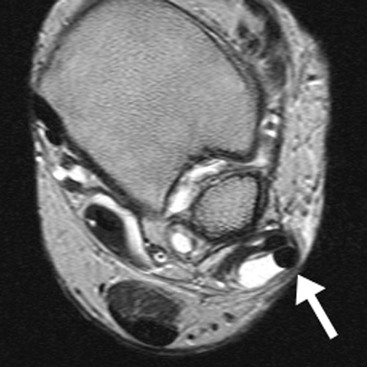

The peroneal tendons pass posterior to the lateral malleolus, where the peroneus brevis (PB) tendon is normally located between the peroneus longus (PL) tendon and the malleolus in the fibular groove. Both tendons are retained by the superior peroneal retinaculum (SPR). The SPR extends from the posterolateral fibular periostium to the Achilles tendon aponeurosis. The PB tendon is prone to longitudinal tears or ‘splits’. In the early stages the PB tendon adopts a semilunar or boomerang shape which progresses to a split with inter-positioning of the PL tendon between the split fibres of PB. Tears of the SPR may lead to peroneal tendon dislocation (Fig. 46-56). Dynamic imaging with ultrasound shows lateral dislocation of the peroneal tendons from the fibular groove with provocative movements.38 A sesamoid os peroneum within the PL tendon is present in a minority of individuals. The os peroneum may be associated with PL tendinopathy or may itself be fractured or inflamed, giving rise to pain. Tears of PL tend to occur at the level of the cuboid tunnel or just distal to an os perineum, if present. Pathology of the anterior ankle tendons, comprising the tibialis anterior, extensor hallucis longus and extensor digitorum longus tendons, is infrequent. Tears of tibialis anterior occur more commonly in older age groups particularly close to the insertion of the medial cuneiform.